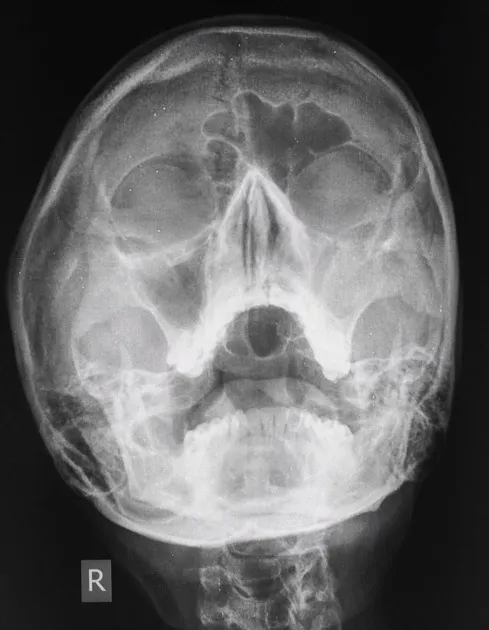

- X-ray Waters view: Air-fluid levels, mucosal thickening (limited utility).

- CT scan: Gold standard; defines anatomy, disease extent, bony erosion.